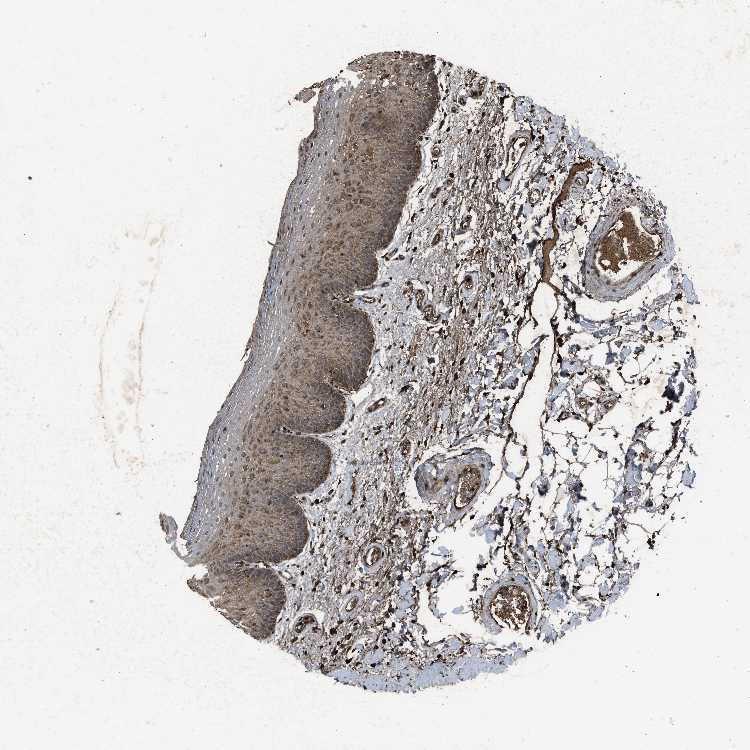

TISSUE PRIMARY DATA ORAL MUCOSA Show tissue menu

Oral mucosa

ORAL MUCOSA - Antibody stainingi

Antibody staining in the annotated cell types in the current human tissue is reported as not detected, low, medium, or high, based on conventional immunohistochemistry profiling in selected tissues. This score is based on the combination of the staining intensity and fraction of stained cells.

Each image is clickable and will lead to virtual microscopy that enables deeper exploration of all samples and also displays staining intensity scores, fraction scores and subcellular localization as well as patient and tissue information for each sample.

Antibody HPA036736Antibody HPA036737Antibody CAB021092

Squamous epithelial cells MediumHighMedium